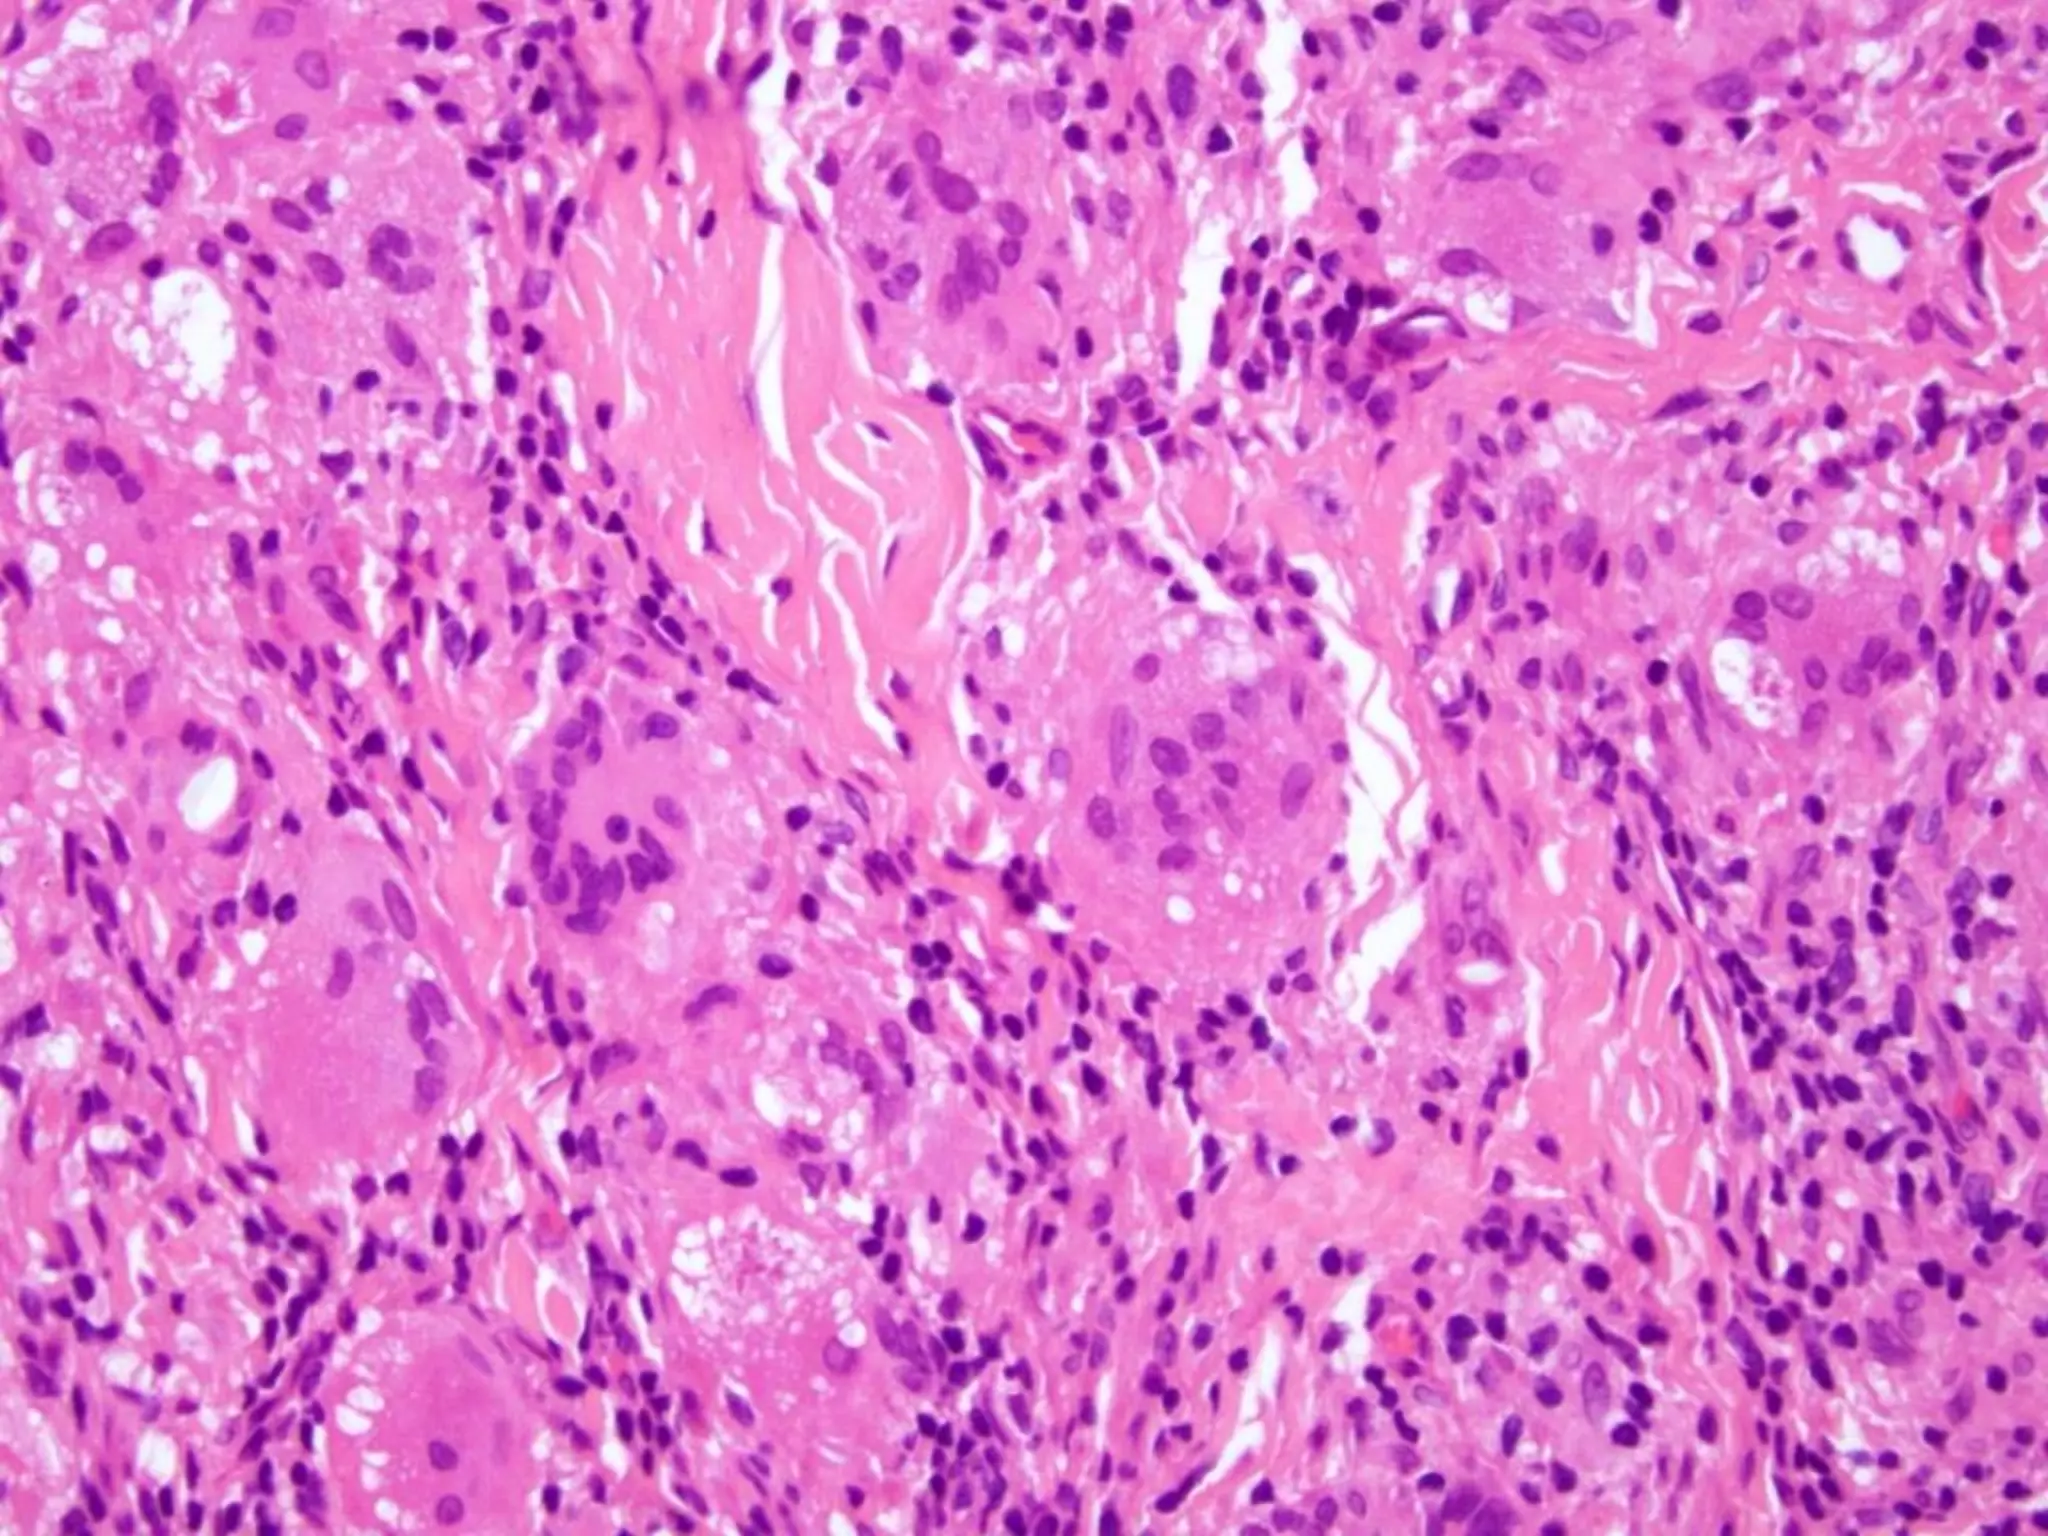

The document provides an overview of dermatopathology, including methods and techniques for skin biopsies such as shave, punch, and ellipse methods. It discusses key terms associated with dermatopathology, such as acantholysis and granulation tissue. Additionally, it references presentations by professionals in the field and essential dermatology resources.